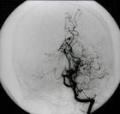

烟雾病